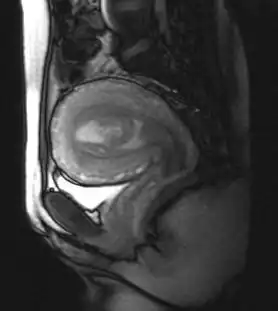

| MRI showing retained products of conception in the first trimester[1] | |